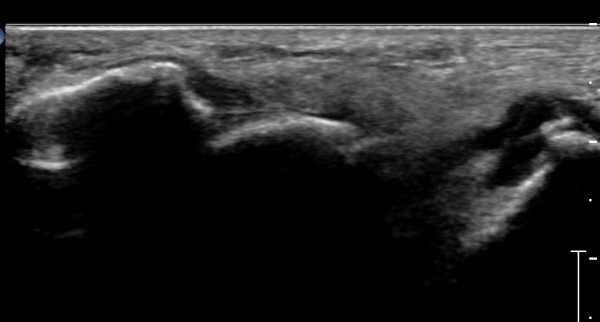

Á¾°ñ Àü¹æµ¹±â Ⱦ´Ü¸é°Ë»ç»ó Àü¹æµ¹±â ¿ÜÃø°ú ³»ÃøºÎ °ß¿­°ñÀýÀÌ °üÂûµÈ´Ù(»çÁø 3).